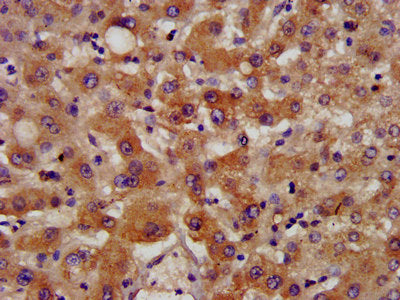

Western Blot | Positive WB detected in: Rat heart tissue | All lanes: NSDHL antibody at 7.2μg/ml | Secondary | Goat polyclonal to rabbit IgG at 1/50000 dilution | Predicted band size: 42 kDa | Observed band size: 42 kDa